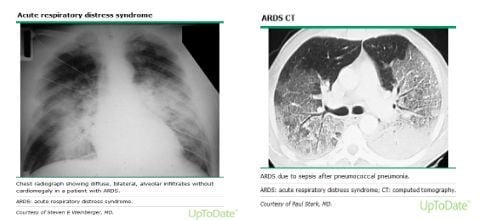

Bên cạnh những dấu hiệu lâm sàng như ho có đờm, ho khan, khó thở… thì một phương tiện cận lâm sàng giúp hỗ trợ chẩn đoán sẽ được chỉ định như chụp X – quang phổi hoặc các phương pháp chẩn đoán hình ảnh khác như chụp cắt lớp vi tính phổi. Những kết quả như hình ảnh X – quang phổi màu trắng hay chụp cắt lớp vi tính phổi thấy những đám màu trắng sẽ giúp định hướng tìm ra nguyên nhân gây bệnh, từ đó sẽ có những phương pháp chữa trị thích hợp. Để điều trị bệnh phổi màu trắng thì bên cạnh việc dùng thuốc theo phác đồ mà bác sĩ điều trị đưa ra thì bệnh nhân cũng cần thay đổi một số thói quen xấu trong phong cách sống của mình như từ bỏ việc hút thuốc lá để giảm thiểu nguy cơ mắc bệnh cho bản thân và cho người xung quanh, cũng như ngăn chặn khả năng xảy ra những biến chứng không mong muốn.

- Hội chứng suy hô hấp cấp tính.

Phổi màu trắng là bệnh lý được chẩn đoán khi bệnh nhân có những biểu hiện bất thường về đường hô hấp như ho, khó thở… cùng với hình ảnh X – quang phổi màu trắng hoặc chụp cắt lớp phổi màu trắng. Đây là một bệnh lý nguy hiểm và có nguy cơ để lại những biến chứng nghiêm trọng với sức khỏe người bệnh, vì vậy cần được phát hiện và chữa trị sớm nhất ngay khi có thể.